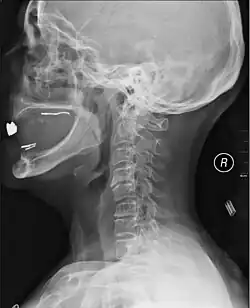

A radiographic evaluation using an X-ray, CT scan, or MRI can determine if there is damage to the spinal column and where it is located.[10] X-rays are commonly available[89] and can detect instability or misalignment of the spinal column, but do not give very detailed images and can miss injuries to the spinal cord or displacement of ligaments or disks that do not have accompanying spinal column damage.[10] Thus when X-ray findings are normal but SCI is still suspected due to pain or SCI symptoms, CT or MRI scans are used.[89] CT gives greater detail than X-rays, but exposes the patient to more radiation,[91] and it still does not give images of the spinal cord or ligaments; MRI shows body structures in the greatest detail.[10] Thus it is the standard for anyone who has neurological deficits found in SCI or is thought to have an unstable spinal column injury.[92]